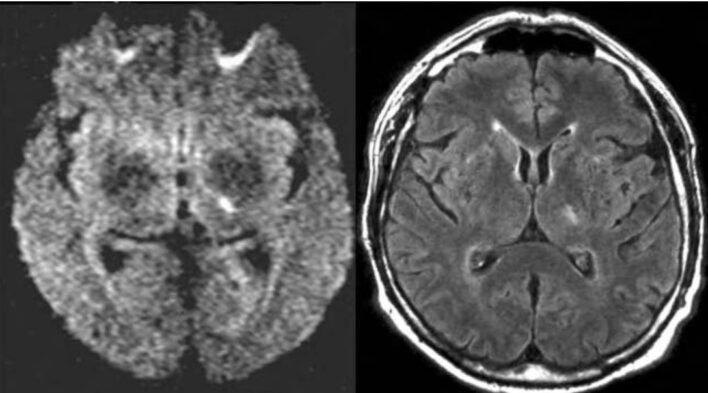

MRI sọ não cho thấy một tổn thương ổ khuyết nhỏ cấp tính ở bao trong bên trái, bên cạnh một số tổn thương chất trắng mạn tính ở cả hai bán cầu. Ngoài ra, có nhiều tổn thương dạng chấm, giảm tín hiệu ở các lát cắt T1w, tăng tín hiệu ở các lát cắt T2w ở chất trắng sâu hai bên được cho là các khoang Virchow-Robin (các khoang quanh thành mạch máu khi các mạch máu đi từ khoang dưới nhện qua nhu mô não) bị giãn rộng. Kích thích từ xuyên sọ và các điện thế kích thích cảm giác vẫn bình thường. Không xác định được nguồn gây thuyên tắc mạch trong siêu âm tim qua lồng ngực, điện tâm đồ bình thường với nhịp xoang bình thường.